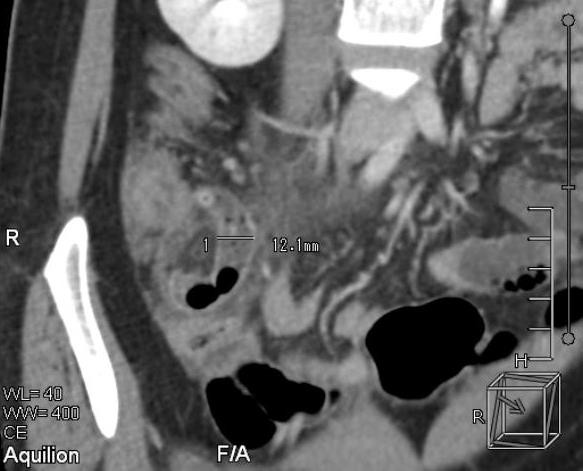

Theo các BS, bệnh nhân nhập viện trong tình trạng đau bụng dưới nhiều và có dấu hiệu nhiễm trùng. Ngay khi tiếp nhận bệnh nhân, các BS đã thăm khám, chỉ định chụp CT bụng và kết luận bệnh nhân bị viêm ruột thừa.

Cứu sống bệnh nhân suýt chết vì rối loạn nhịp tim hiếm gặp ảnh 1Vị trí bị viêm ruột thừa cấp của bệnh nhân.